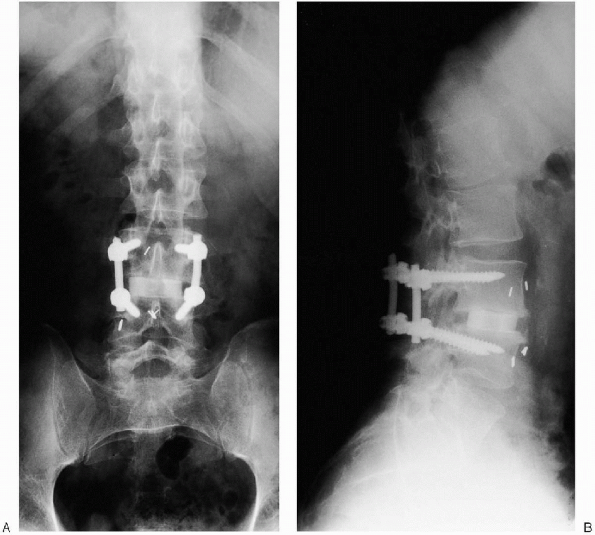

osteophytic changes (Figs. 19-4 and 19-5). Restoration of the disc space height was achieved with an ALIF using a femoral ring allograft as a structural support (Fig. 19-29). Postoperative radiographs demonstrate the final pedicle screw construct for a one level fusion (Fig. 19-30).

![]() |

FIGURE 19-29. Anteroposterior x-ray film after anterior lumbar interbody fusion (ALIF) (arrow at femoral ring).

FIGURE 19-30. A: Anteroposterior x-ray film of final construct. B: Lateral x-ray film of final construct.